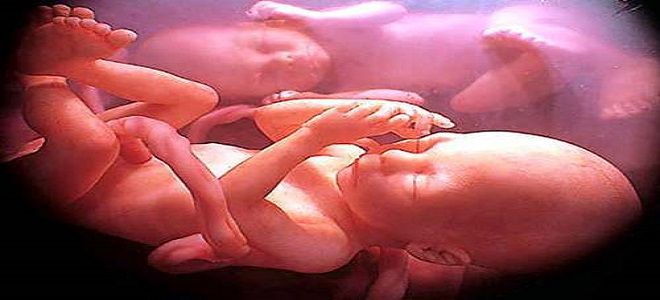

Многоплодная беременность — это сложный процесс, вызывающий интерес и беспокойство у будущих родителей. В статье рассмотрим признаки многоплодной беременности на ранних сроках, особенности зачатия, шансы на успешное вынашивание и возможные осложнения. Понимание этих аспектов поможет родителям подготовиться к материнству и отцовству, а также осознать важность медицинского наблюдения во время беременности.

Многоплодная беременность представляет собой уникальное и сложное состояние, которое требует особого внимания как со стороны будущих родителей, так и медицинских специалистов. Эксперты отмечают, что шансы на зачатие нескольких эмбрионов значительно увеличиваются с возрастом женщины и при использовании вспомогательных репродуктивных технологий. Однако многоплодная беременность сопряжена с рядом возможных осложнений, таких как преждевременные роды, преэклампсия и низкий вес при рождении. Врачи подчеркивают важность регулярного мониторинга состояния матери и плодов, чтобы минимизировать риски и обеспечить здоровье как матери, так и детей. Психологическая поддержка также играет ключевую роль в успешном прохождении этого периода, так как многоплодная беременность может вызывать значительный стресс и тревогу у будущих родителей.

При зачатии дизиготных близнецов на свет появляется двойня, которую генетики часто называют разнояйцевой. Этот процесс происходит в результате одновременного оплодотворения двух различных яйцеклеток. Созревание этих половых клеток может происходить как в одном яичнике, так и в разных. Наследственная предрасположенность к появлению дизиготных близнецов может передаваться по материнской линии. Дети, которые появляются на свет в результате такой беременности, могут быть как одного пола, так и разного.

Говоря о беременности двойней, врачи отмечают, что при разнояйцевой двойне в материнской утробе всегда формируются две плаценты. Обычно они располагаются близко друг к другу, иногда даже соприкасаются, но их всегда можно разделить. Каждый зародыш находится в отдельном плодовместилище (плодной оболочке), которые разделены перегородкой. В составе этого анатомического образования присутствуют две хориальные и две амниотические оболочки.